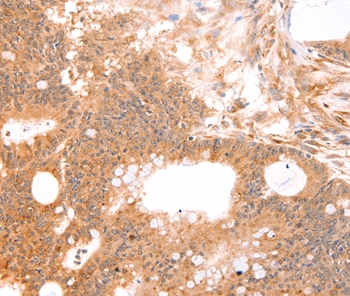

分类: 科研抗体货号: P42784别名: OGC; SLC20A4应用: WB,IHC反应种属: Human